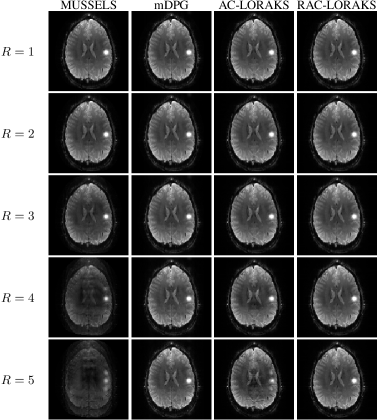

Figure 1 shows ACS data and reconstruction results from the in vivo gradient-echo EPI brain data with an axial slice orientation. The ACS data in this case does not have strong artifacts, although close inspection does reveal that ACS ghost artifacts are present. This can be further appreciated in Supporting Information Fig. S4 where the same images are shown with amplified image intensity to highlight ghost characteristics in the image background. As can be seen, all ghost correction methods work well at smaller acceleration factors, although performance begins to degrade at larger acceleration factors. We observe that, compared to other methods, the visual quality of the MUSSELS reconstruction seems to degrade most rapidly as a function of acceleration factor, which is consistent with previous observations [18]. The mDPG method had qualitatively better performance than MUSSELS in this case. However, a close inspection of the images reveals that the mDPG results are not entirely ghost-free even for the unaccelerated () case. This may be expected due to the artifacts and mismatches that are present in the ACS data. Although mDPG does not attempt to correct the ACS artifacts, it should be noted that the original DPG method does try to correct them through pre-processing. Results showing the qualitative performance of the original DPG method are shown in Supporting Information Fig. S5, where we observe that the ghost artifacts still exist, though as expected, are less prominent than were observed for mDPG. In spite of the ACS artifacts, the AC-LORAKS reconstruction still has good performance at low acceleration factors and does a good job of suppressing ghosts in the background regions of the image at all acceleration factors, although exhibits substantial degradation in image quality at the highest acceleration factors (with artifacts similar to those observed for highly-accelerated parallel imaging reconstructions). However, the RAC-LORAKS reconstruction appears to have much higher quality than the other methods, even at very high acceleration factors like . (Note that when , the effective acceleration factor is when each readout gradient polarity is considered separately. This leads to a highly ill-posed inverse problem).

Figure 1: ACS data and reconstruction results for in vivo gradient-echo EPI brain data with an axial slice orientation for different parallel imaging acceleration factors. Note that the first four acceleration factors (-) were acquired from one subject during a single scan session while the last two acceleration factors () were acquired from a different subject on a different day, which explains the visual discontinuity between these cases.